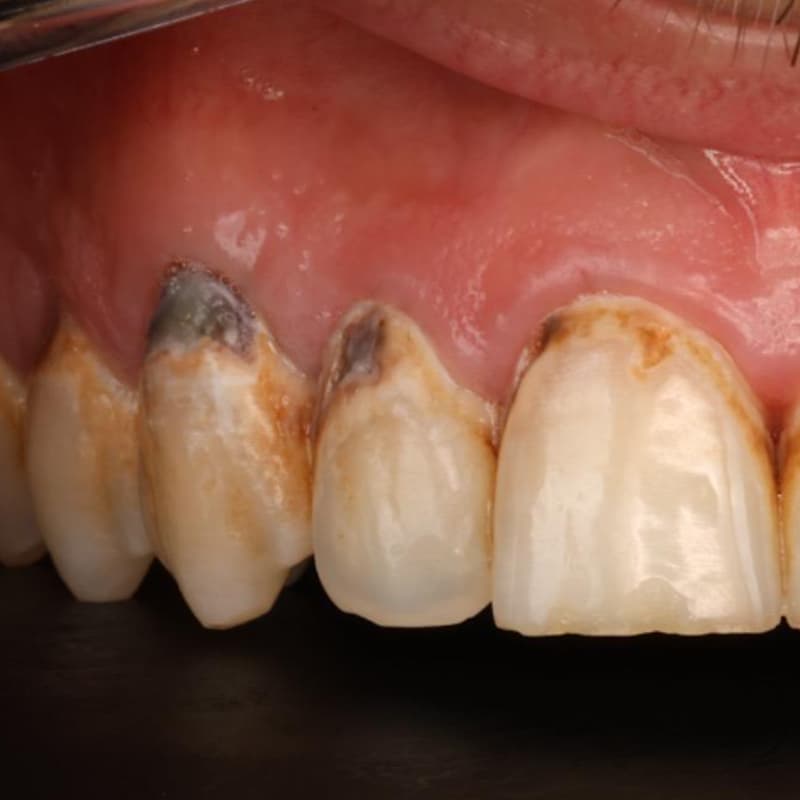

En esta imagen se muestra cómo el azúcar y el ácido de estas bebidas afecta a los dientes.